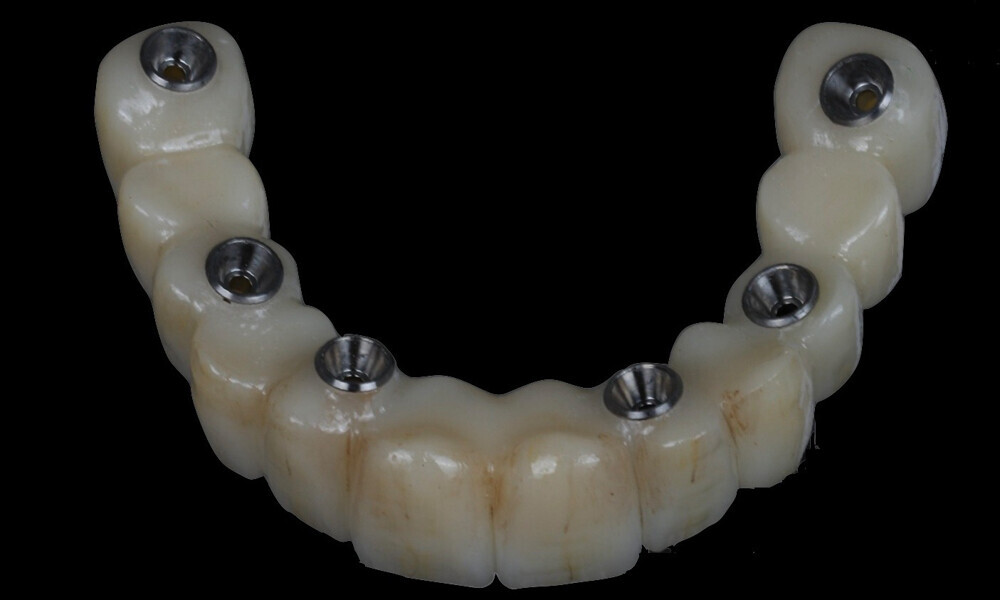

During the next visit, the milled prototype and verification jig were tried in, and the design and manufacturing of the final prosthesis were completed (Figs. 47 & 48). The final abutment utilised was Variobase for bridge (Straumann), placed on top of the screw-retained abutments. The material chosen for the final prosthesis was monolithic zirconia (Figs. 49 & 50).